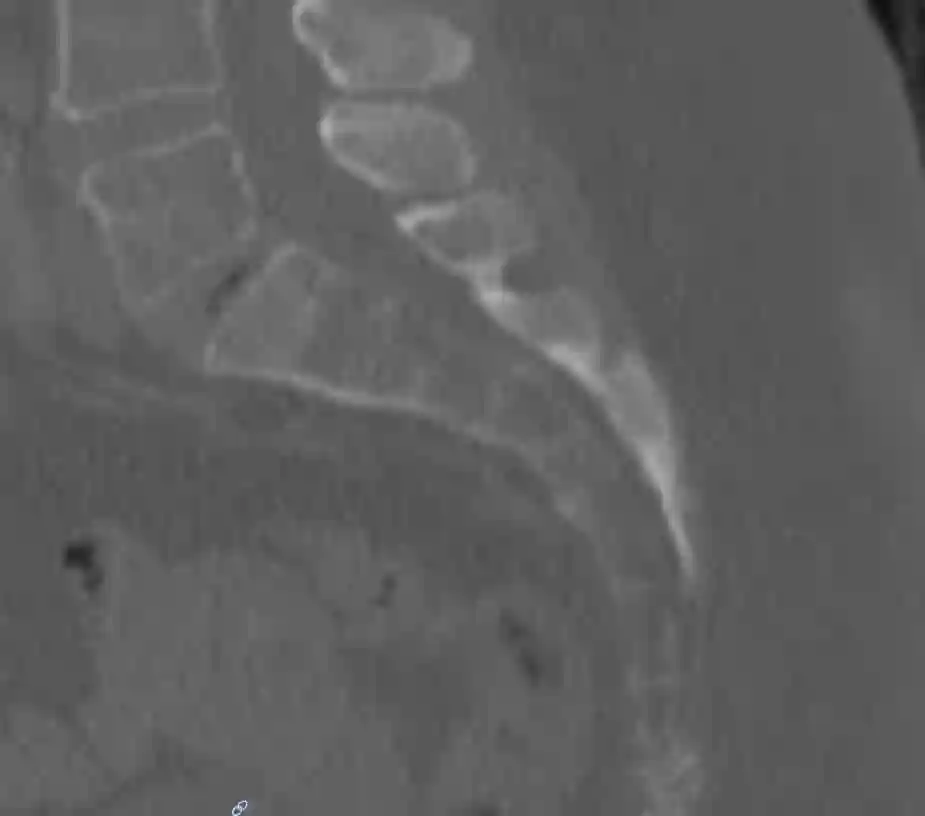

Sagittales CT Bild des Os sacrum

Sagittales CT Bild des Os sacrum.